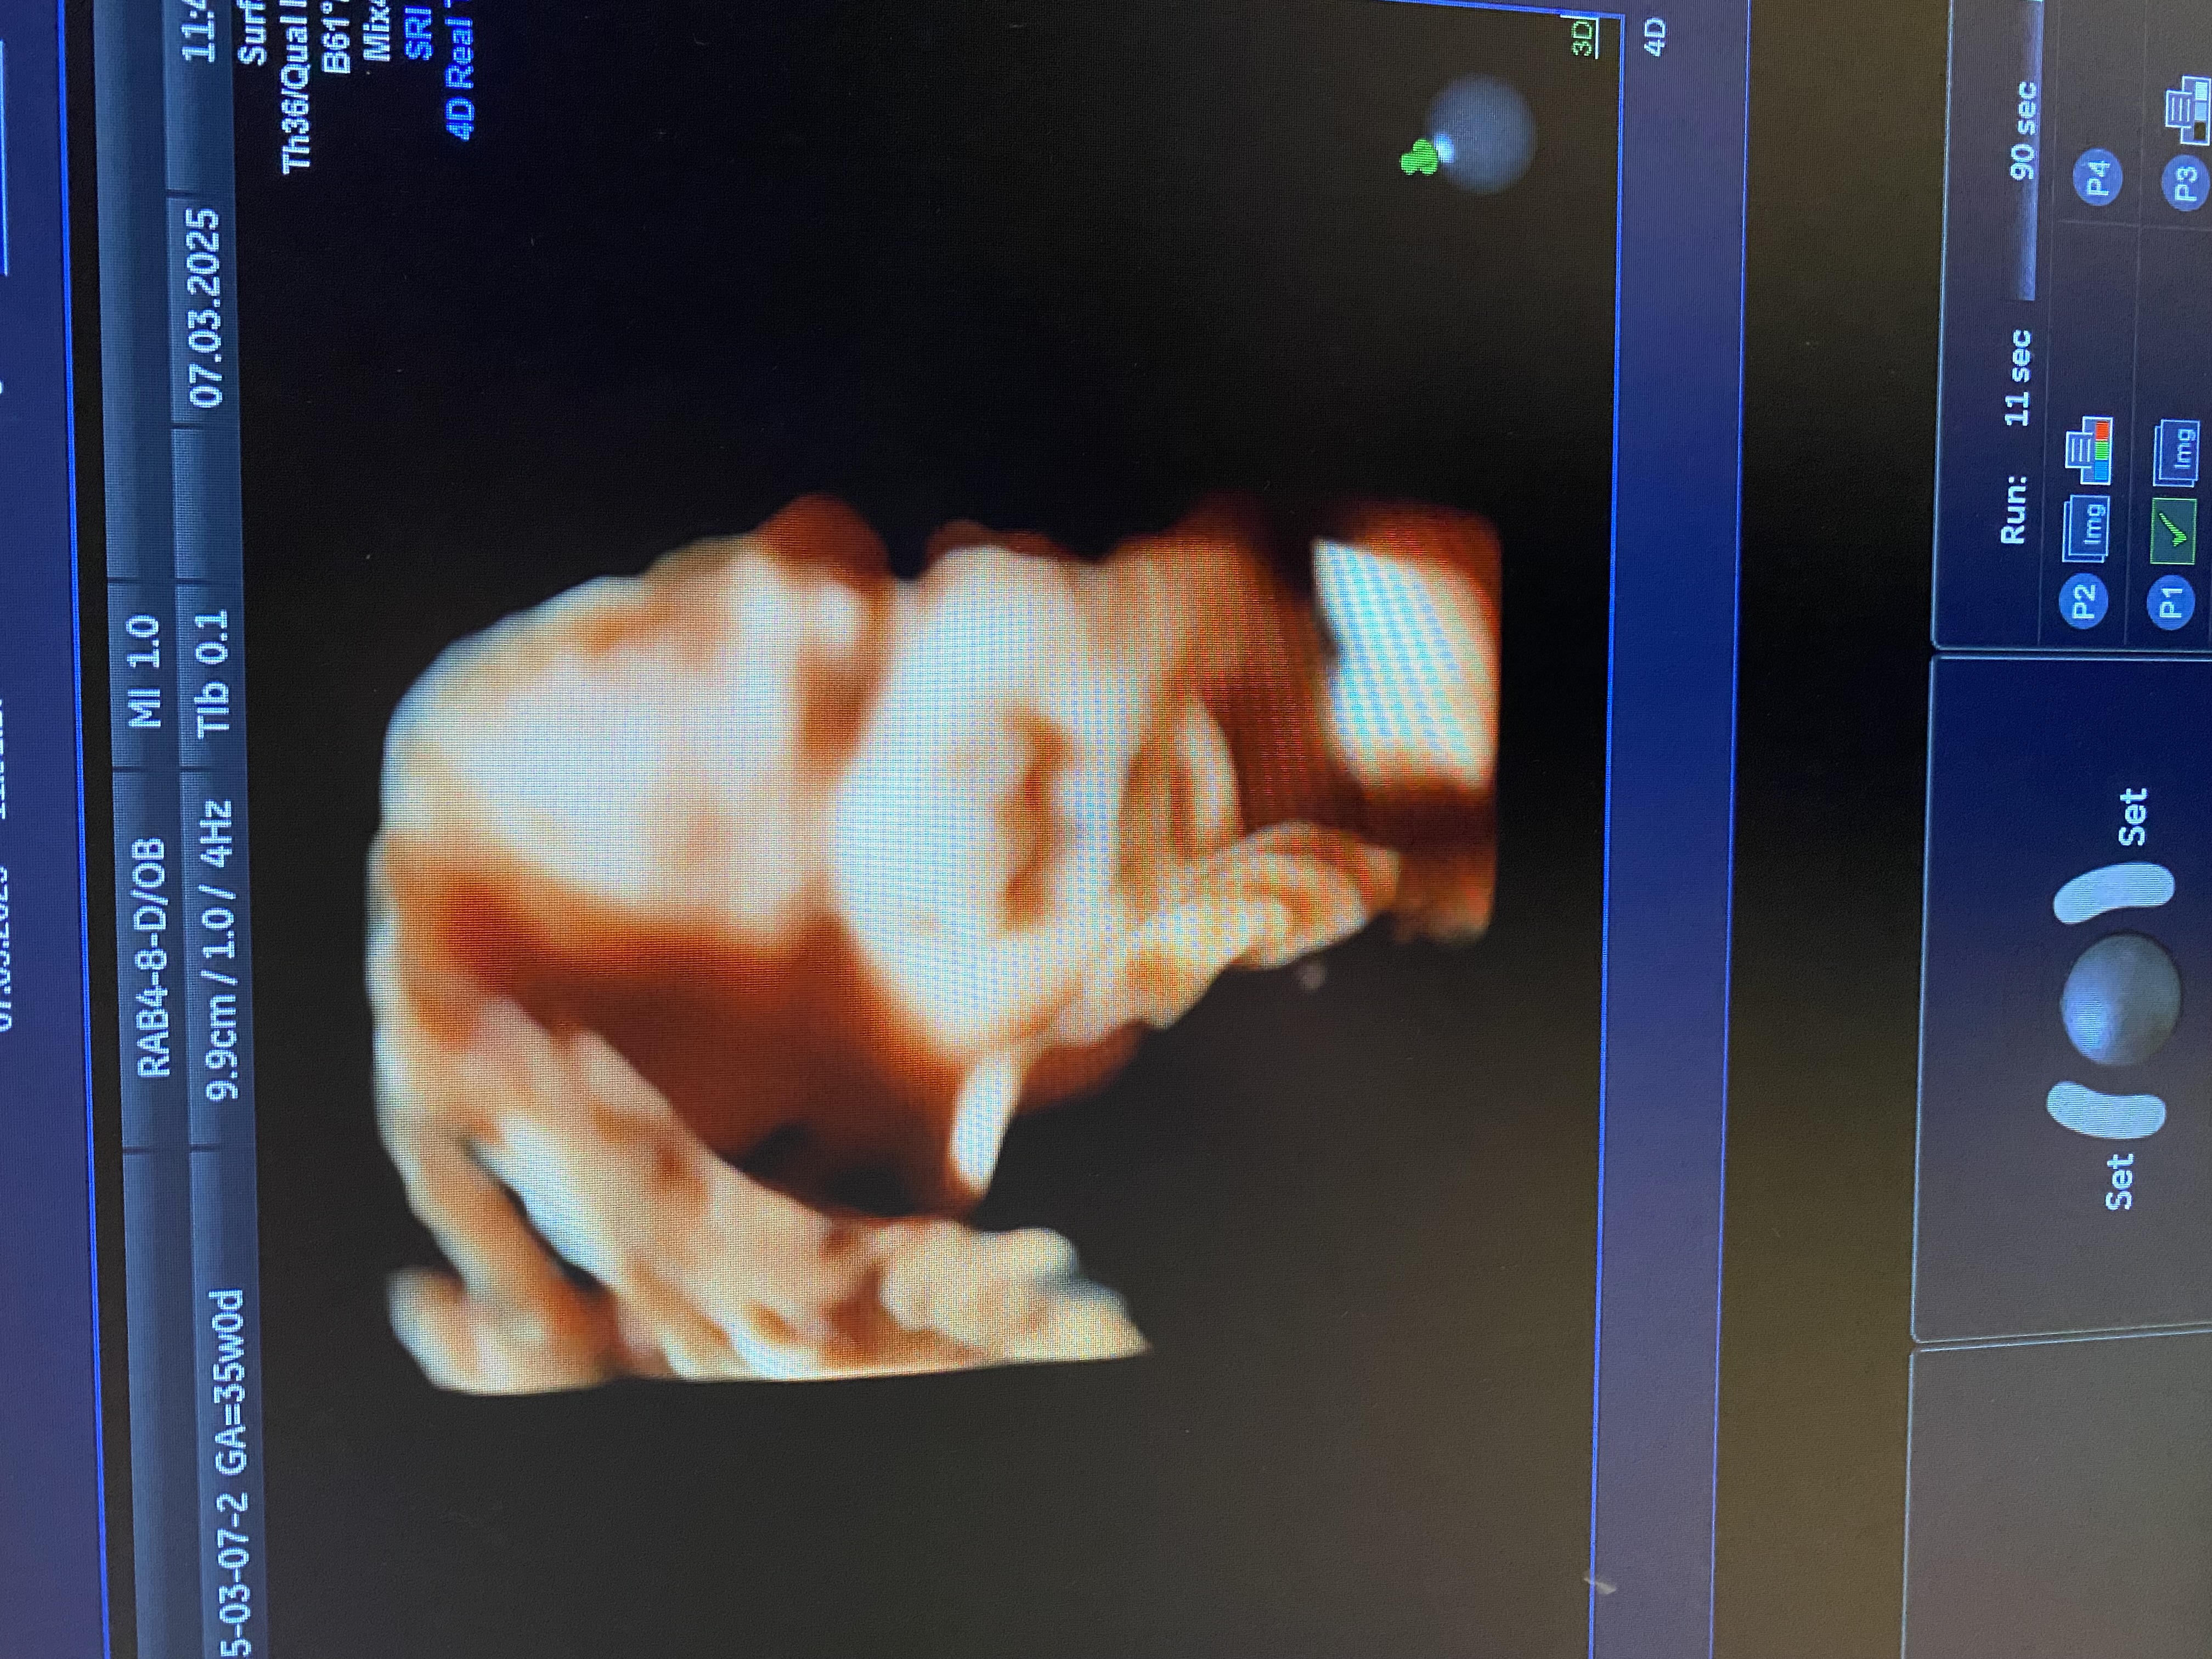

УЗИ. 35 недель и 4 дня

УЗИ, КТГ, доплерКакая она уже большая ☺️🥹. Вес 2570 грамм.

Это было первое УЗИ, на котором я уже перестала понимать где и что находится, такая она большая, разглядела только пальцы и голову😅